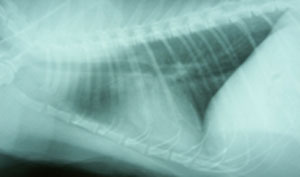

胸部X線検査所見:肺野にスリガラス状陰影、心陰影は不鮮鋭だが形状異常なし(図4)。

図4 症例2の初診時胸部X線写真。肺野にスリガラス状陰影、心陰影は不鮮鋭だが形状異常はみられなかった。